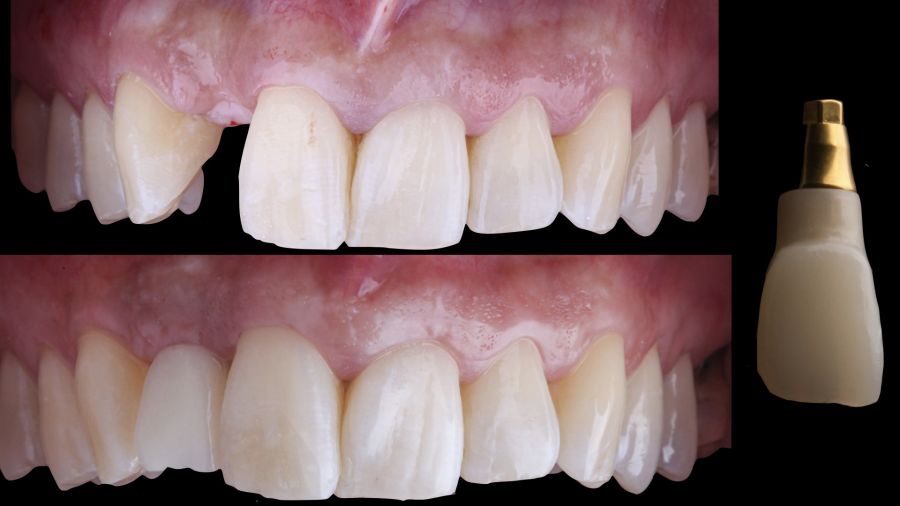

-Fase III: tres meses tras la colocación del implante, la situación del tejido blando era favorable (Figuras 5 y 6). Se tomó una impresión digital mediante escáner intraoral para la realización de un provisional atornillado de polimetilmetacrilato (PMMA). Respecto a la corona implantaria definitiva se realizó una restauración cemento-atornillada con una interfase de titanio nitrurado adaptando el diseño al perfil de emergencia ya consolidado con la prótesis provisional. La corona se realizó por CAD-CAM en zirconio con reducción completa y estratificación de cerámica feldespática de recubrimiento para zirconio (Figura 7).